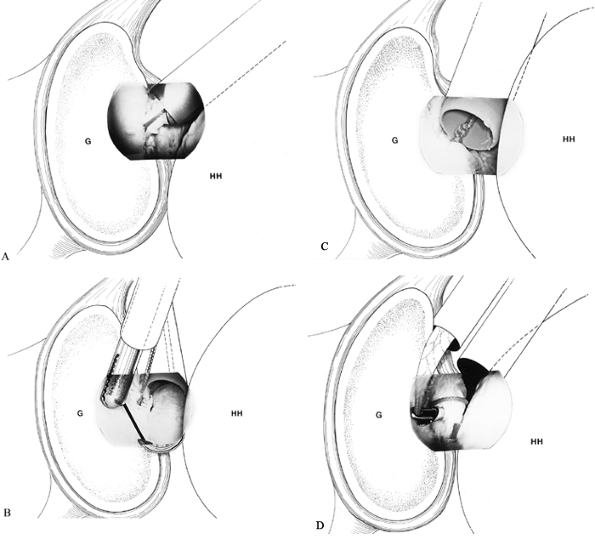

glenohumeral ligaments function in a reciprocal fashion, acting as

extremes of motion (37,113,114 and 115,160). O’ Brien et al. (113,114)

compared the IGHL to a hammock; its anterior and posterior bands should

tighten at terminal external rotation with the arm abducted 90° (Fig. 80.5).

![]() |

Figure 80.5. The IGHL controls glenohumeral instability in a manner analogous to a hammock. A: With the arm in 90° of abduction, the IGHL supports the humeral head inferiorly. B: With external rotation, the anterior band of the ligament prevents anterior translation of the humeral head. C:

The posterior band functions in a similar fashion with internal rotation to prevent posterior translation of the humeral head. (From Warner JJP, Caborn DN. Overview of Shoulder Instability. Crit Rev Phys Rehabil Med 1992;4:145, with permission.) |